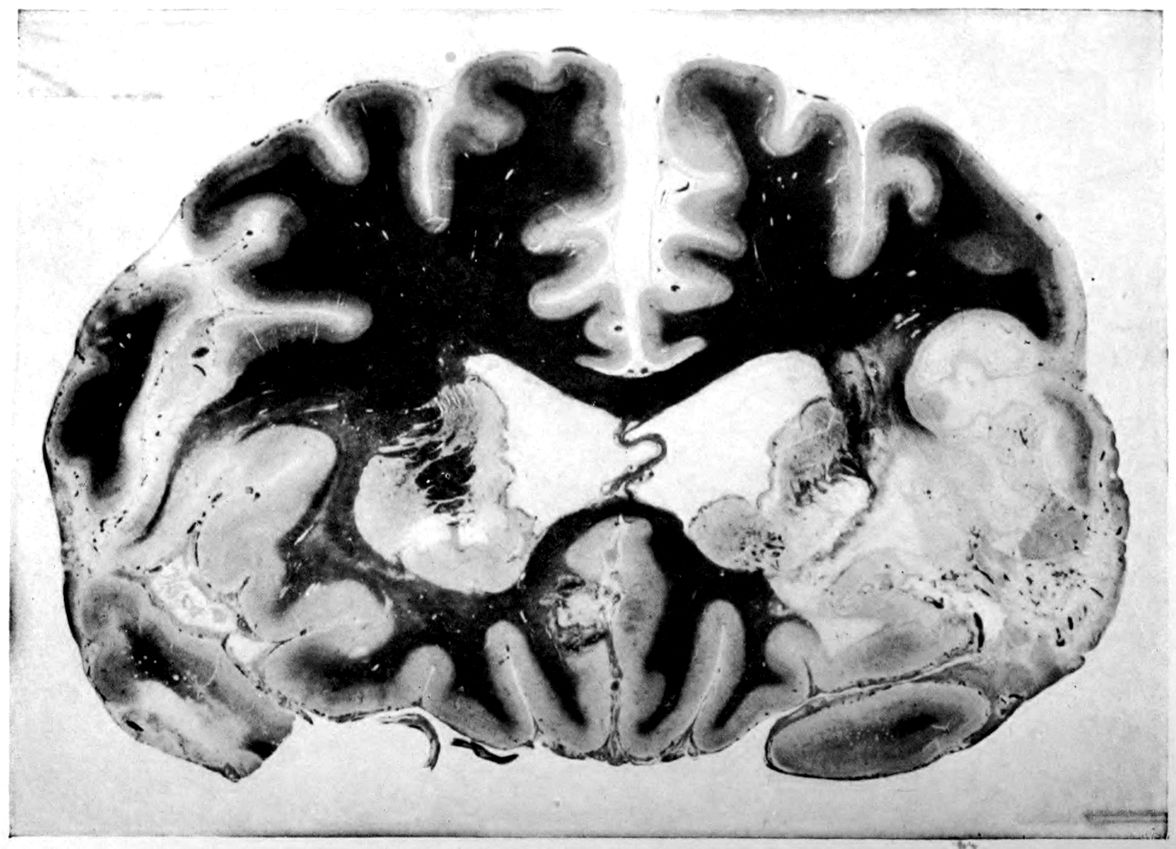

Case 4. James Pierce was an almshouse transfer to the Danvers Hospital in his fiftieth year. He died three years later. The accompanying brain pictures demonstrate so extensive a lesion of the left hemisphere that it is of great interest to determine if possible the genesis and course of his disease. It appears that syphilis had been acquired somewhere about the age of 38 or 40, so that the total duration of the process was between 13 and 15 years. In Pierce’s forty-third or forty-fourth year, he had a shock while walking in the streets of his native city, whereupon he was subsequently transferred to the Danvers Hospital, whose data have been summed up as follows (we are obliged to Dr. Charles T. Ryder for these data):

Head: Calvarium of moderate thickness; diploë present; dura slightly adherent over bregmatic region. Longitudinal sinus contains cruor clot. Dura is somewhat thickened and slightly more opaque than normal. Pacchionian granulations, small but fairly numerous. Pia contains throughout a considerable excess of clear 44serous fluid. The convolutions in general are of good breadth and proportion. There is an atrophic area roughly circular in outline and about 2 cm. in diameter in the posterior part of the right third frontal convolution corresponding to Broca’s area on the opposite hemisphere. The space thus formed is filled with edema held by the pia. On the left side is a similar subpial collection which covers the site of the posterior portions of all of the third frontal convolutions, parts of the lower end of the precentral convolution, and the whole of the first temporal convolution, which have disappeared entirely. The basal vessels show slight changes.

Cerebellum and basal ganglia are grossly normal.

The spinal membranes are negative. The regions of the pyramidal tracts in the cord are firm, project slightly from surface of section, and are china white.

Summary: Here is a picture made up almost purely of Vascular Neurosyphilis, with Secondary Spinal (Pyramidal Tract) Changes. Doubtless the genesis of this picture is allied to that of Case 1 (Alice Morton) and to that of the terminal vascular complications in a tabetic, Case 2 (Francis Garfield).

The absence of meningeal and parenchymatous (i.e., outside the region of necrosis produced by the vascular disease) lesions is characteristic of an important group of neurosyphilitic diseases. It is clear that the case, although one of extensive lesions, is not one of diffuse lesions in the sense of Case 1 (Alice Morton).

Vascular neurosyphilis—effects of syphilitic thrombosis of Sylvian artery 10 years before death. (Case 4.)

Case 4. (See previous figure for brain lesion.) Three levels of the spinal cord showing unilateral pyramidal tract sclerosis, 10 years after cerebral thrombosis.